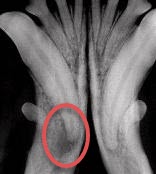

The x-ray on the right is an image of an impacted tooth.

One of these canine teeth (fangs) has dental disease that is not visible without an X-ray. Which one?

The x-ray below shows an infection at the root of the fang on the left.